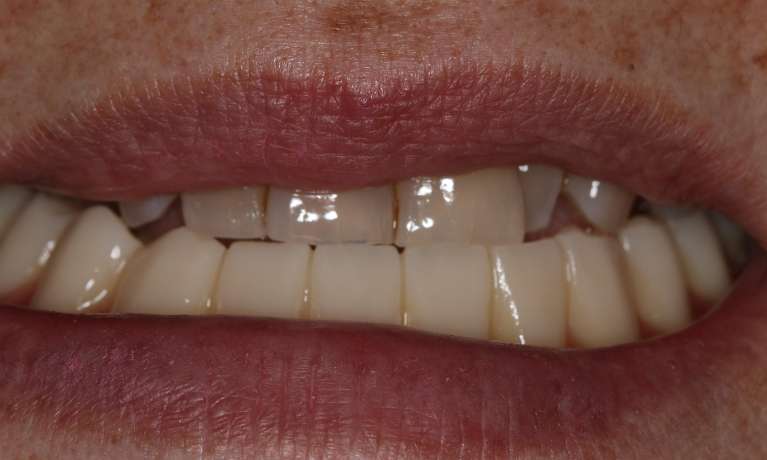

The upper and lower sets of teeth are removed and replaced with removable dentures that are securely held in place by dental implants. This provides improved stability, comfort, and function - leading to a patient who was thrilled with their new smile!

Implant-retained dentures have transformed our patient's smile. This permanent solution provides stability, comfort and a natural look, making it a fantastic option for those missing teeth. Our patient is thrilled with the results - and we are too.

Implant-retained dentures have given this patient a smile that's built to last. This permanent solution not only looks natural but also provides the comfort and security needed to enjoy life to the fullest.